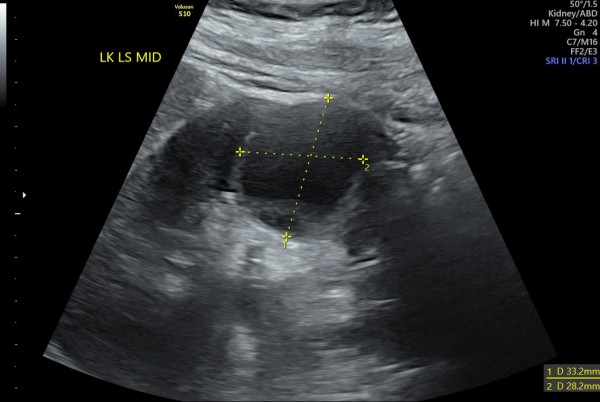

Czy mógłby ktoś mi powiedzieć czy 'infekcja cysty' to poprawna interpretacja załączonego USG?

Załączniki